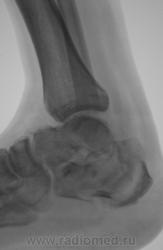

Лечение состояло из "множества рентгенов" и гипса. Срок - 5 месяцев.

Сейчас думают об остеомиелите.

Контуры пяточной кости относительно четкие, разрежение структуры пяточного бугра, в проекции перелома уплотнение структуры кости( имею в виду последние снимки).Клиника остеомиелита есть?

Во-первых, деформация пяточной кости; во-вторых, отсутствие консолидации, через некоторое время и ложный сустав сформируется. Неоднородное уплотнение костной структуры в теле кости может быть обусловдено как остеомиелитом, так и перераспределением нагрузки.

Признаков остеомиелита не вижу, только консолидир перелом с неуд стоянием отломков.